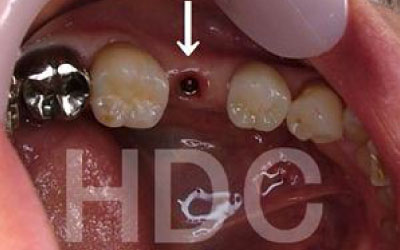

CT撮影を行うことで、骨や歯の状態を立体的に把握でき、各部位の距離を正確に測定することができます。

インプラント治療では、骨の厚さや傾斜、神経の位置などを事前に詳細に確認することで、より安全で確実な治療計画が立てられます。

しかし、事前にCT撮影を行って神経との距離を正確に把握した上で計画を立てることで、リスクは大幅に軽減できます。

さらに当院では、必要以上に骨を削らないよう専用のストッパーも併用しています。